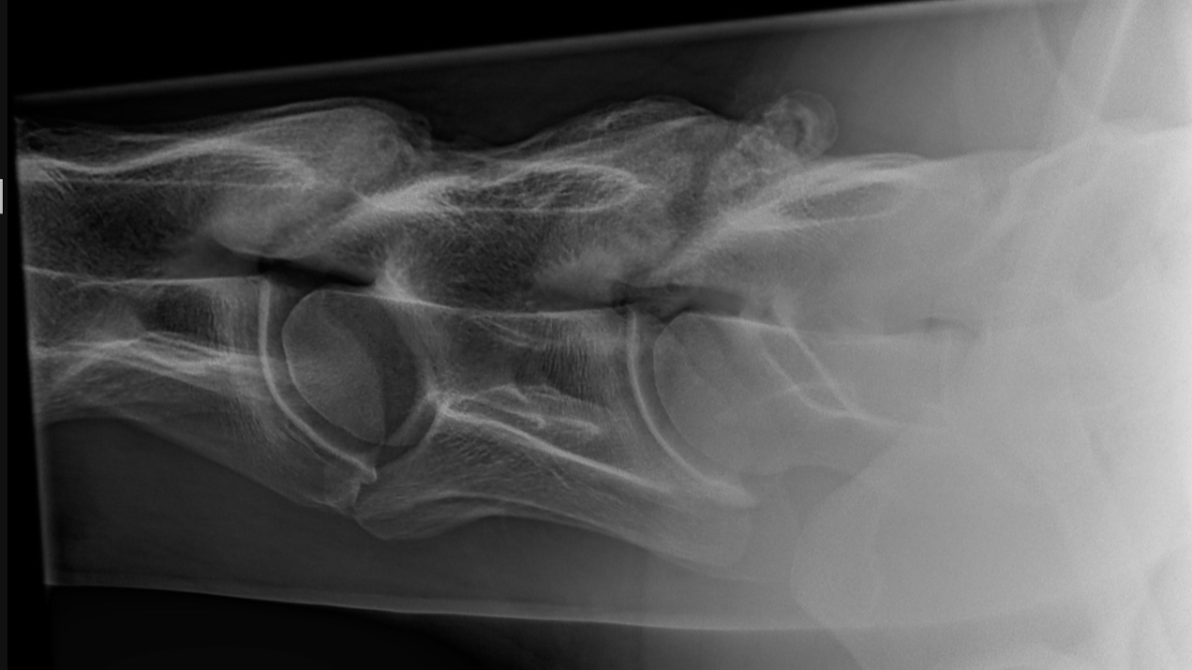

Cervicale Radiografie

Cervicale röntgenopnames vragen om nuance en klinische context zonder te over- of onderdiagnosticeren.

Klinisch relevante aandoeningen of anatomische variatie?

Cervicale röntgenopnames zijn een vaste waarde in kreupelheidsonderzoek én in pre-purchase exams — maar hoe betrouwbaar zijn onze interpretaties eigenlijk? In deze aflevering onderzoeken we waar de grens ligt tussen pathologische bevindingen en normale anatomische variatie.

We bespreken waarom cervicale afwijkingen vaak uitdagend zijn om correct te interpreteren en hoe je als dierenarts voorkomt dat je te veel — of net te weinig — betekenis hecht aan wat je op de beelden ziet.